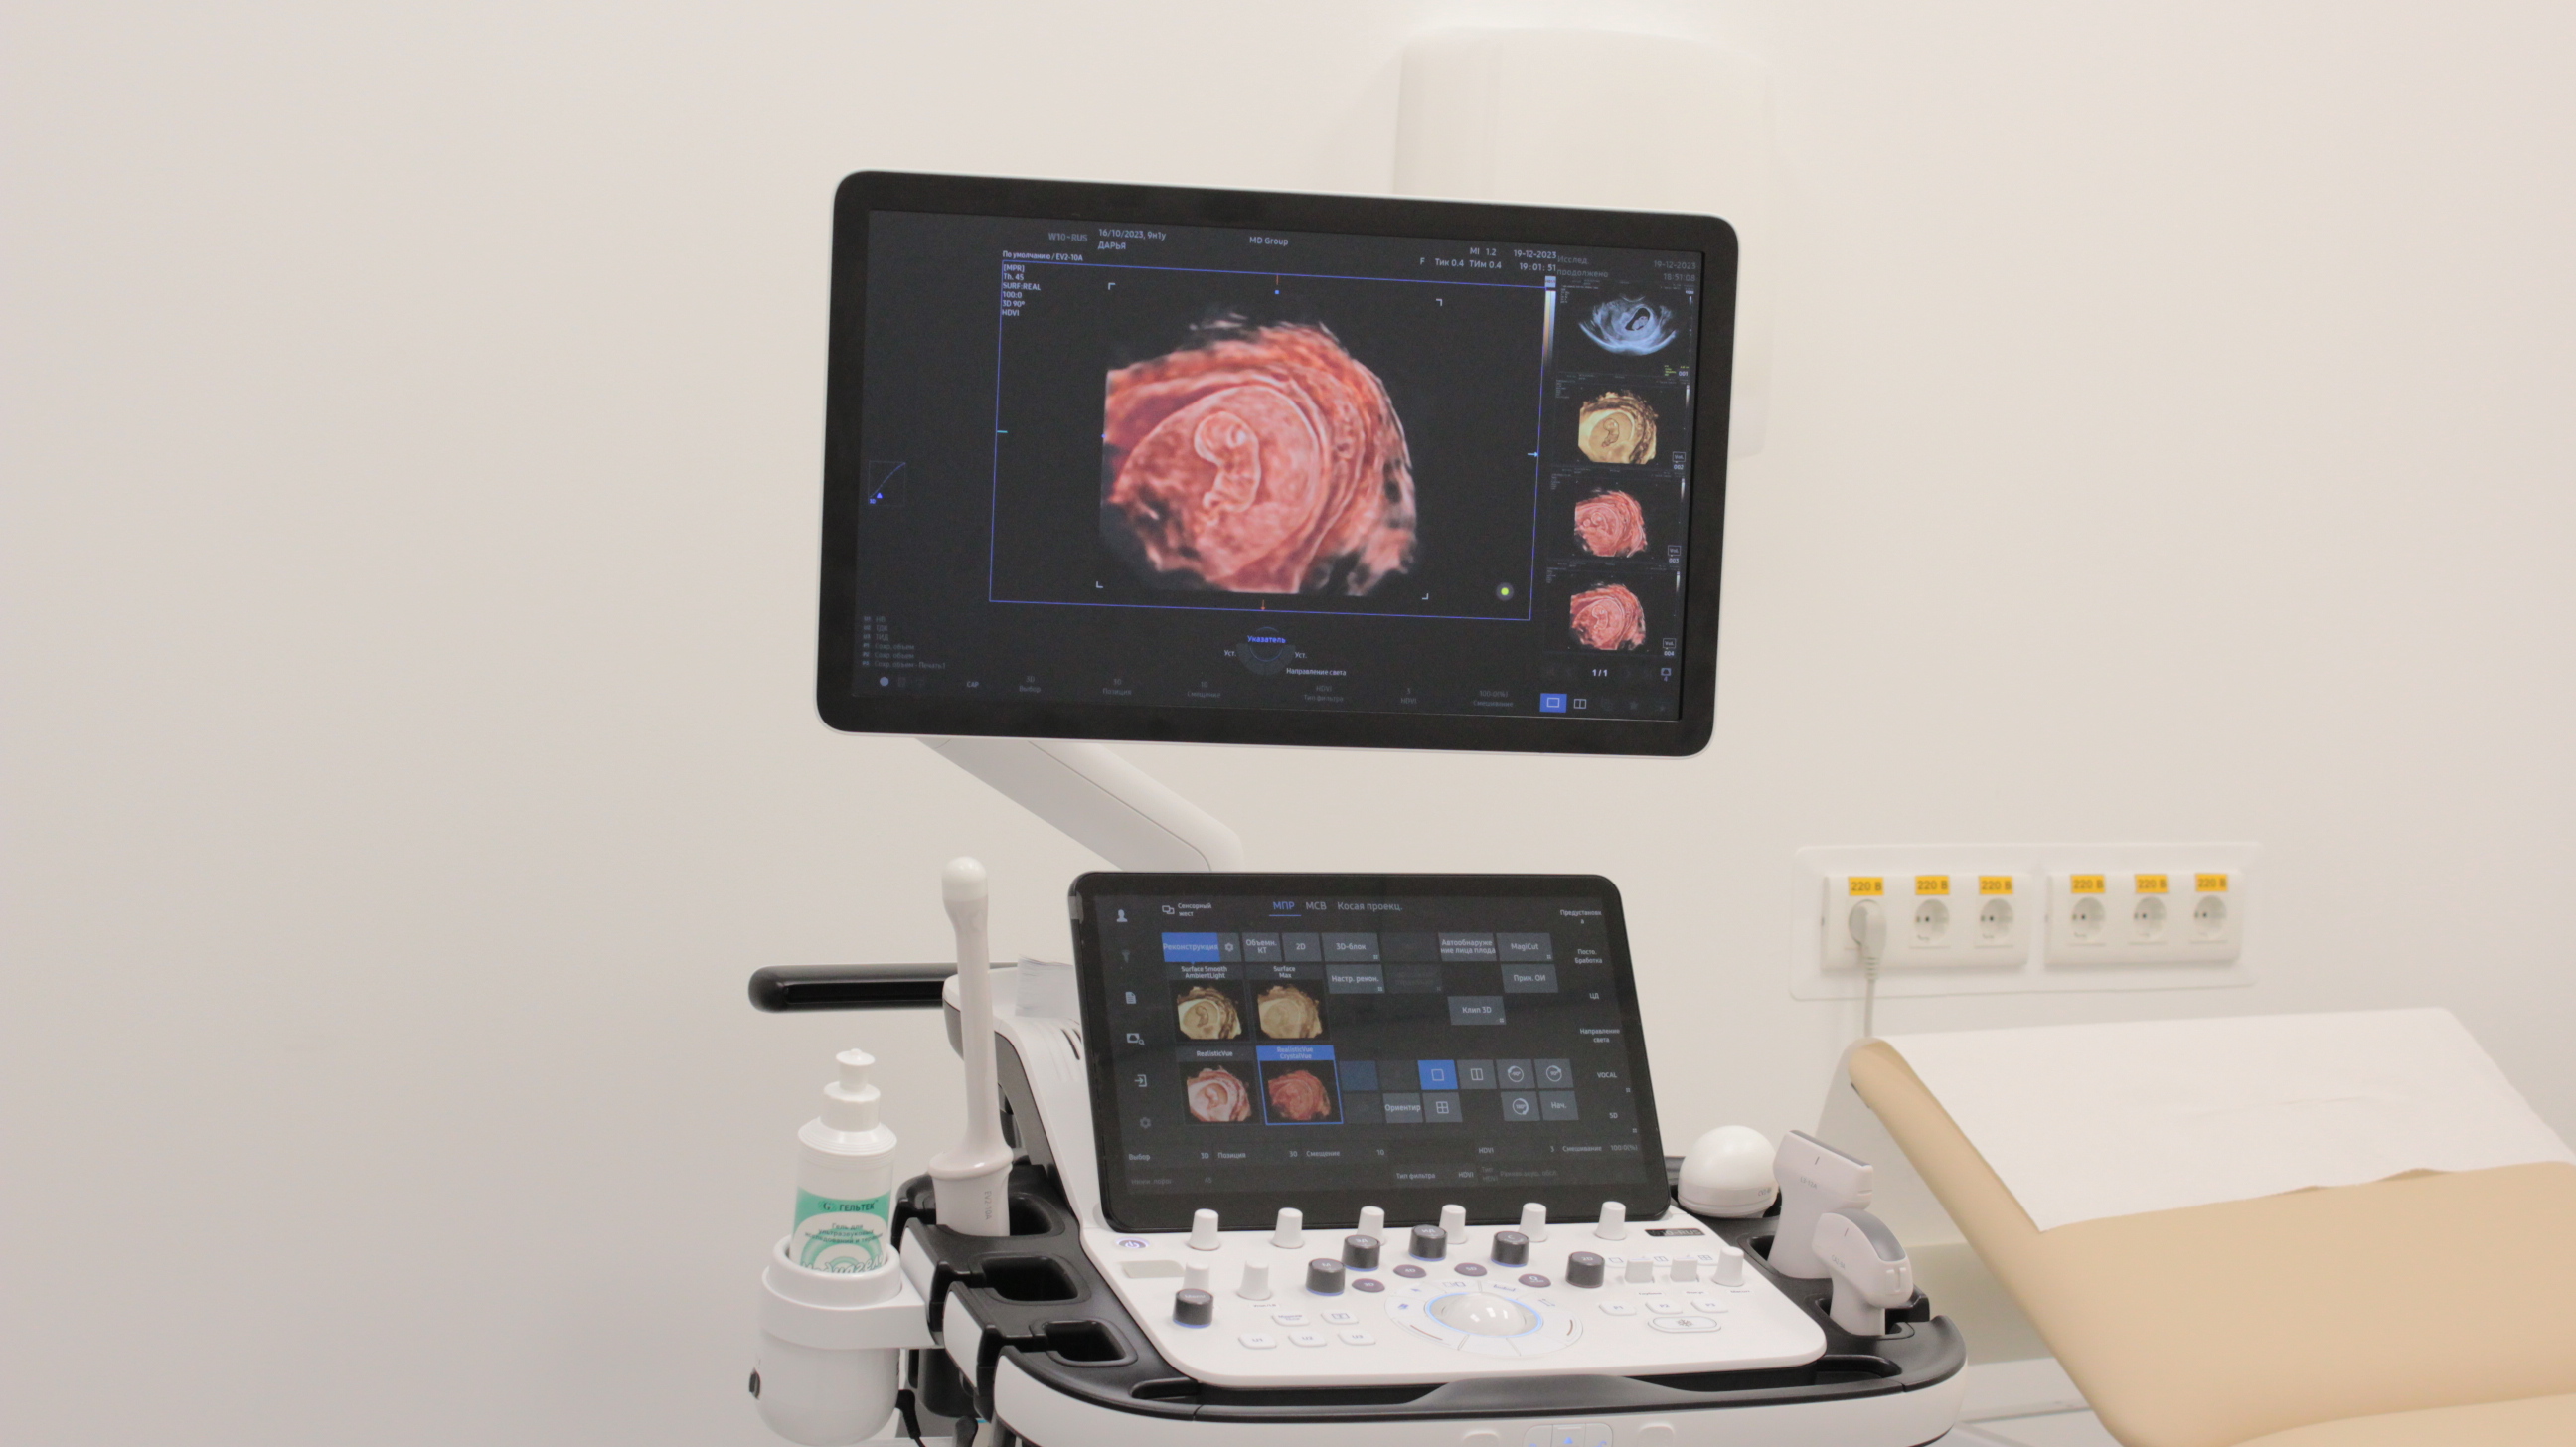

Ультразвуковое исследование – это наиболее информативный метод диагностики состояния плода и беременной женщины. В «Мать и дитя» оно проводится с помощью современного ультразвукового оборудования, которое формирует максимально детализированное изображение. УЗИ дает возможность обнаружить особенности развития малыша на самой ранней стадии. Метод абсолютно безопасен и может выполняться любое количество раз.

При необходимости врач назначает дополнительные измерения, оценивает кровоток (допплерометрия) или проводит экспертное исследование, чтобы уточнить состояние плода и выбрать оптимальную тактику наблюдения.